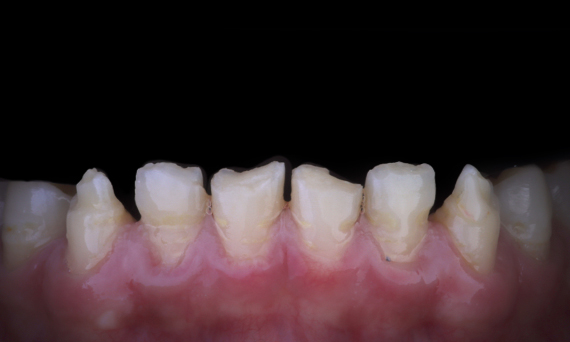

Amélogenèse imparfaite

Restauration complète de la bouche avec 28 restaurations tout céramique

Un cas particulier et prolongé de malocclusion squelettique de classe II et d’amélogenèse imparfaite généralisée chez un adolescent a été référé pour une réhabilitation prothétique. L’objectif du traitement était de préparer la structure dentaire restante, d’éliminer les contre-dépouilles et de faire de la place pour des couronnes entièrement en céramique couvrant toute la dentine et simulant l’émail perdu.

Avant : Situation initiale avant le traitement orthodontie.

Après : Résultat final, 1 semaine après l’opération.

Alexander Declerck, (DDS, MSc)

Laethem-Saint-Martin, Belgique